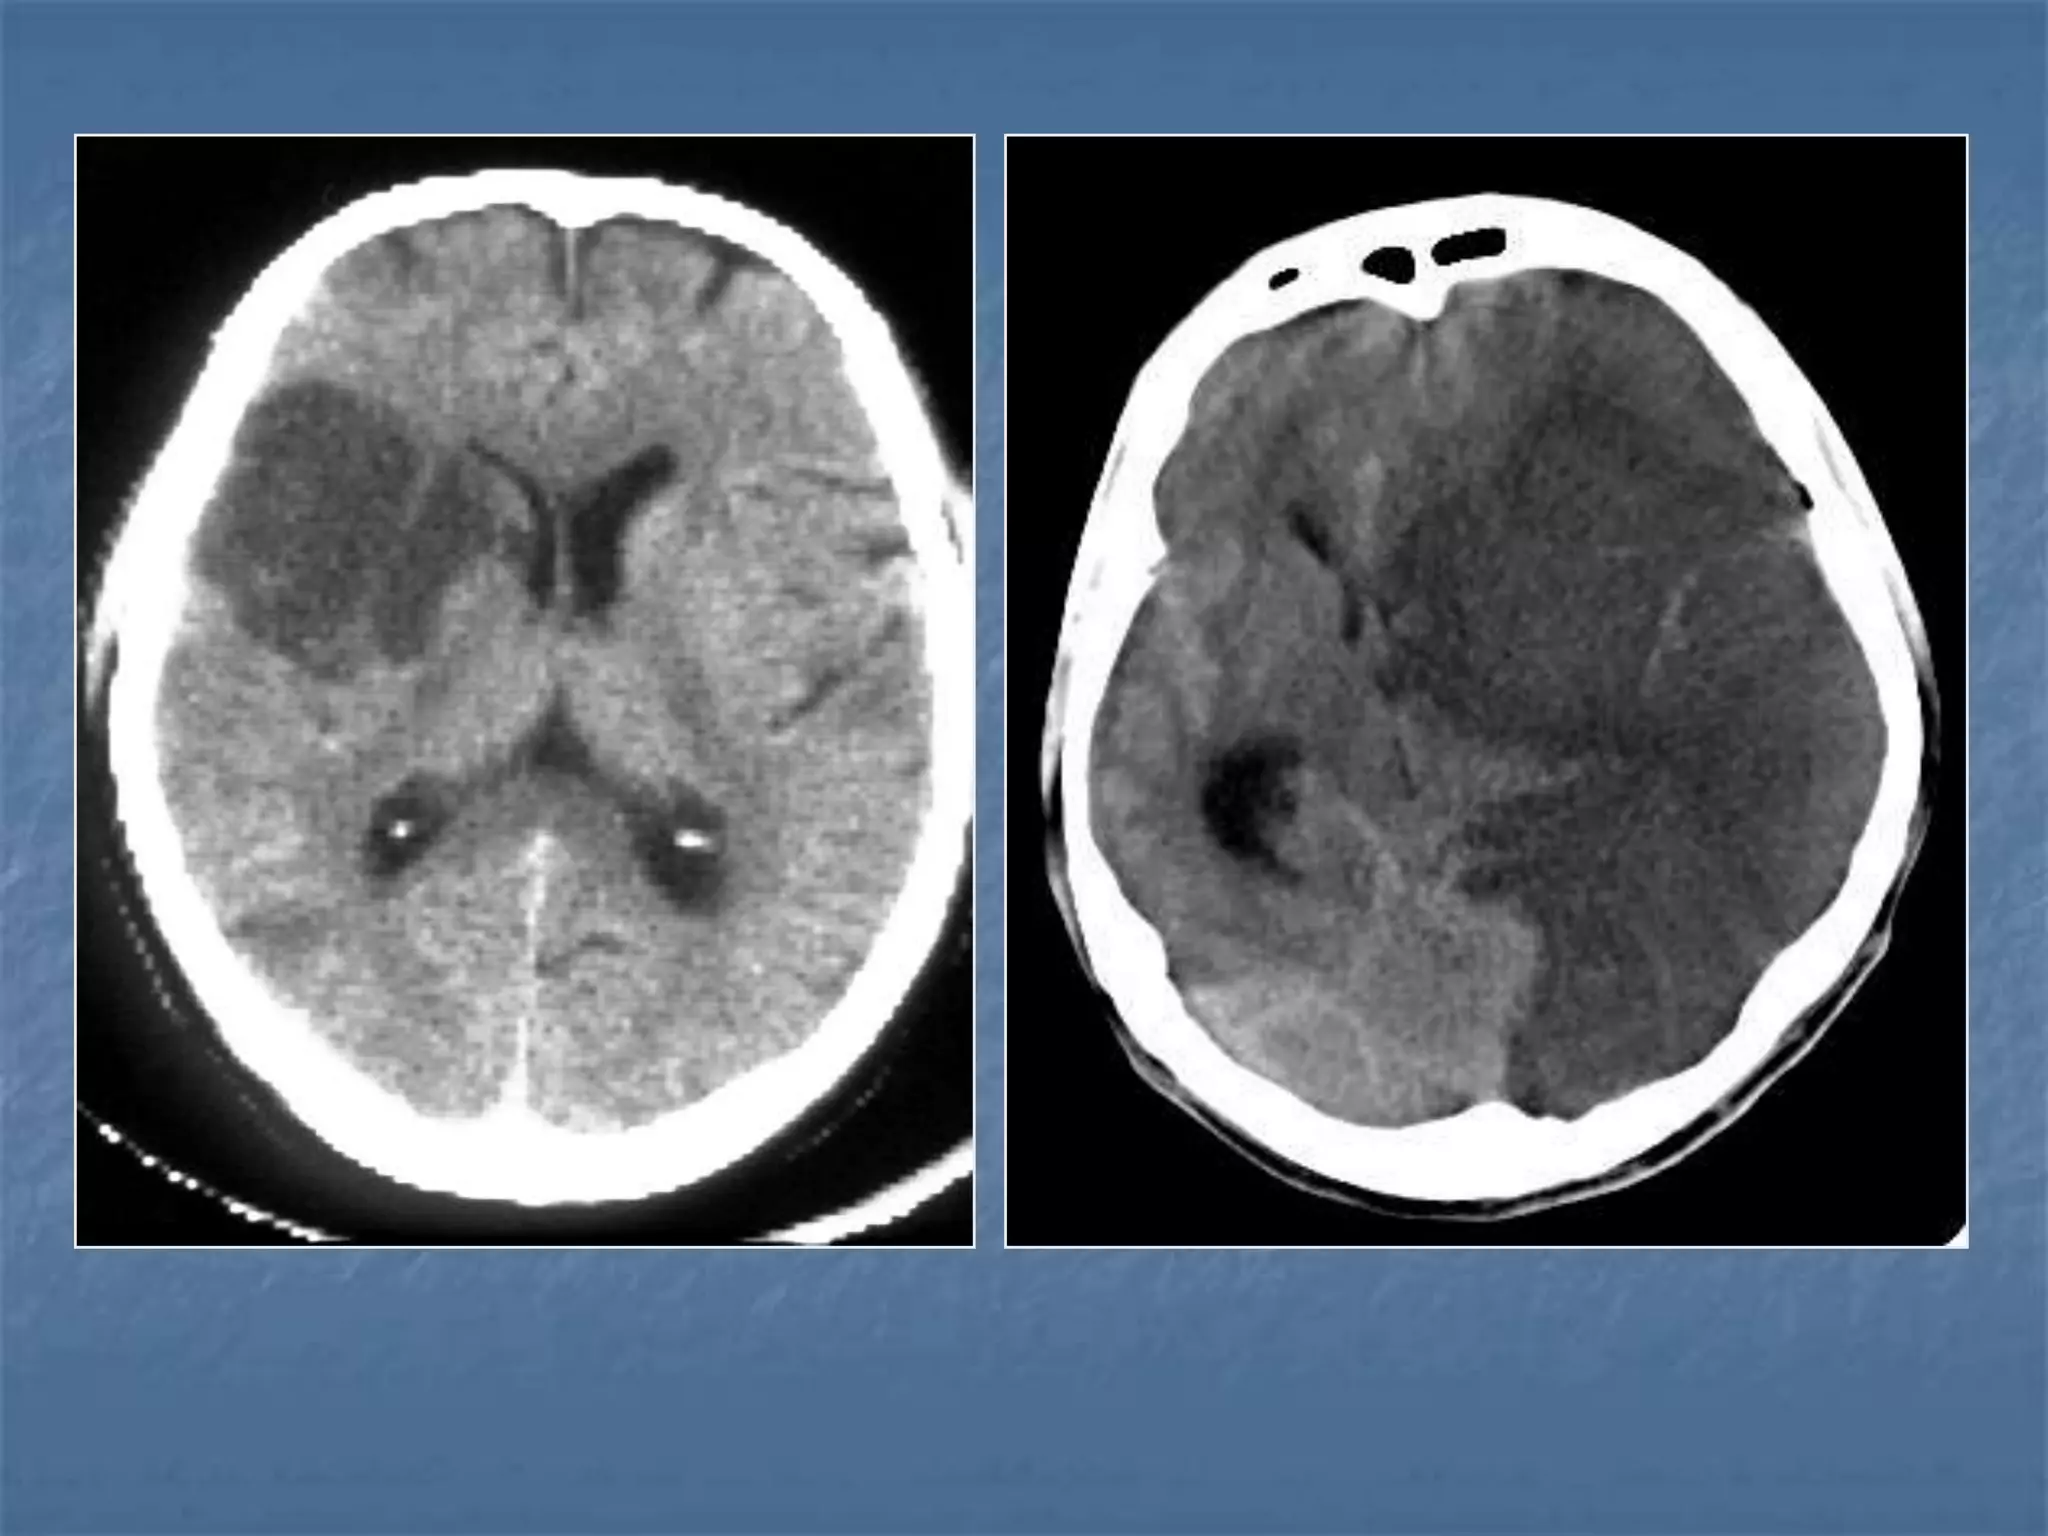

Epidural Hematoma

 An epidural hematoma is usually associated with a skull

fracture. It often occurs when an impact fractures the

calvarium. The fractured bone lacerates a dural artery or a

venous sinus. The blood from the ruptured vessel collects

between the skull and dura. On CT, the hematoma forms a

hyperdense biconvex mass. It is usually uniformly high

density but may contain hypodense foci due to active

bleeding. Since an epidural hematoma is extradural it can

cross the dural reflections unlike a subdural hematoma.

However an epidural hematoma usually does not cross

suture lines where the dura tightly adheres to the adjacent

skull

Diffuse Axonal Injury

 Diffuse axonal injury is often referred to as "shear injury". It is the most

common cause of significant morbidity in CNS trauma. Fifty percent of all

primary intra-axial injuries are diffuse axonal injuries. Acceleration,

deceleration and rotational forces cause portions of the brain with

different densities to move relative to each other resulting in the

deformation and tearing of axons. Immediate loss of consciousness is

typical of these injuries. The CT of a patient with diffuse axonal injury may

be normal despite the patient's presentation with a profound neurological

deficit. With CT, diffuse axonal injury may appear as ill-defined areas of

high density or hemorrhage in characteristic locations. The injury occurs in

a sequential pattern of locations based on the severity of the trauma. The

following list of diffuse axonal injury locations is ordered with the most

likely location listed first followed by successively less likely locations:

- Subcortical white matter

- Posterior limb internal capsule

- Corpus callosum

- Dorsolateral midbrain

SUBACUTE SDH

ACUTE ON CHRONIC SDH